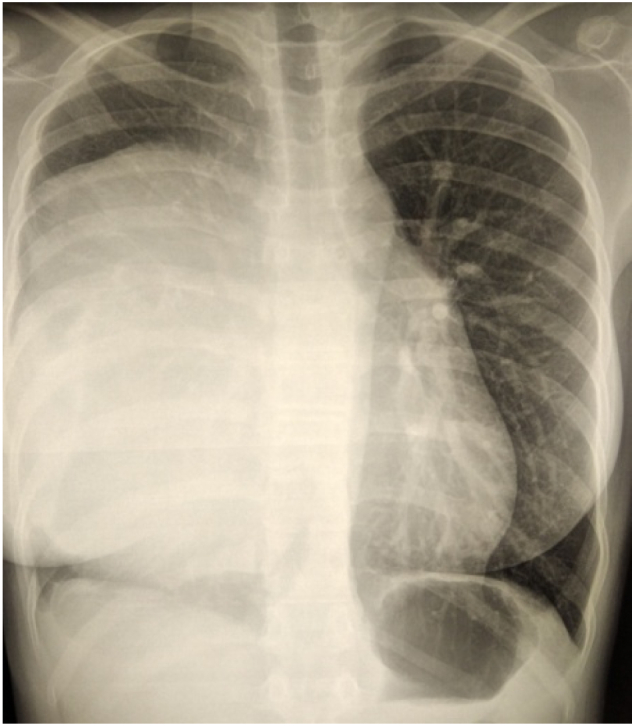

Fig. 1.

Chest X-Ray showed an homogeneous opacity occupying the middle and the lower zone of the right hemithorax.

A 14-year- old girl, without comorbidities, has complained of dyspnea for 2 years was admitted to our hospital. The chest examination revealed a right parasternal swelling. The chest X-Ray has showed an homogeneous opacity occupying the middle and the lower zone of the right hemithorax (Fig. 1). A computed tomography of the chest revealed a giant heterogenous right-sided anterior mediastinal mass mesuring 16 × 13 × 19 cm. The mass contained multiple cysts with calcifications and fat, illustrating a mature teratoma which compressed the heart, the superior vena cava, the right pulmonary artery and the pulmonary vena (Fig. 2). Therefore, the tumor has been considered resectable. We have decided to extirpate the tumor by median sternotomy with right anterior thoracotomy extension (hemiclamshell approach). There were widespread adhesions between the tumor, the pericardium and the right phrenic nerve. We have punctured the tumor and we have aspirated its contents (Fig. 3A and B). The tumor was totally resected in bloc along with a cuff of pericardium, phrenic nerve and azygos vena (Fig. 3C). The right pericardial defect has been repaired with Mersilene mesh (Fig. 3D). The histopathology of the tumor revealed a mature cystic teratoma. The postoperative course was uneventful during a 7 day in hospital stay. After 24 month follow-up, the patient denied any shortness of breath, chest pain or limitation on her daily activities with a perfect chest X-Ray (Fig. 4).